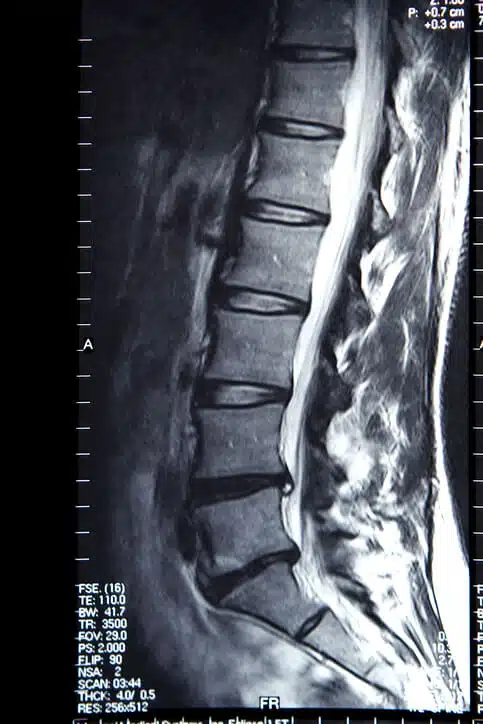

Probleem 2: Beeldvorming

• Radiologische beeldvorming (MRI/CT/Röntgen) wordt momenteel niet aangeraden voor selectie.

• • Afwijking ≠ Pijn: Het zien van artrose of degeneratie betekent niet automatisch dat daar de pijn vandaan komt.

• • Geen afwijking ≠ Geen pijn: Patiënten met een 'schone' scan kunnen ernstige pijnklachten hebben.

Radiologische beeldvorming (MRI/CT/Röntgen) wordt momenteel niet aangeraden voor selectie.

Afwijking ≠ Pijn: Het zien van artrose of degeneratie betekent niet automatisch dat daar de pijn vandaan komt.

Geen afwijking ≠ Geen pijn: Patiënten met een 'schone' scan kunnen ernstige pijnklachten hebben.